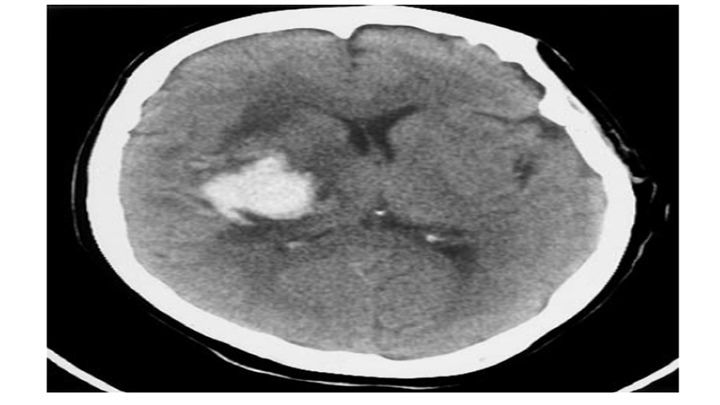

基底节区血肿,壳核消失(可与对侧比较观察),周围可见片状低密度区。在几天的时间里,血肿外围低密度区会逐渐增大。水肿部分因为血管的浆液性渗出从出血灶向外延伸至白质,部分是由于周围神经组织对血块的水肿反应。